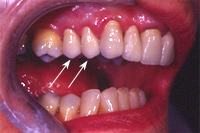

Ein 31 Jahre alter Patient zeigt einen starke Zahnfleisch-Rückgang im Oberkiefer (Abb. 1 und 3) und wir beschliessen, diese Rezessionen zu behandeln.

Der Erfolg der Behandlung ist deutlich in den Abb. 2 und 4 zu sehen. Sehr augenfällig konnte die Situation um den Eckzahn im linken Oberkiefer verbessert werden (vergleiche dazu Abb. 3 vorher und Abb. 4 nachher).